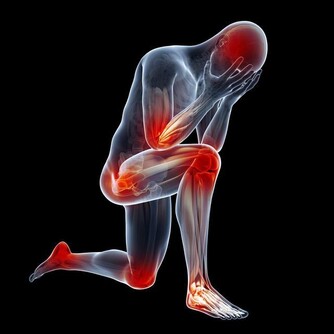

15 、疼痛。

美國癌症協會表示,隨著年齡增加,身體疼痛會增多。

但是身體某部位莫名出現疼痛并持續一周以上時,應盡快查明原因,

因為無緣無故的疼痛可能是癌症徵兆。

比如,長期腹痛是大腸癌的症狀,胸部疼痛可能是肺癌引起的,骨頭酸痛則可能是癌症轉移的症狀。

劉俊田指出,胰腺癌會表現在上腹區,

如臍周或右上腹出現頑固性鈍痛 或絞痛,可陣發,也可呈持續性,通常會逐漸加重,向腰背部放射。